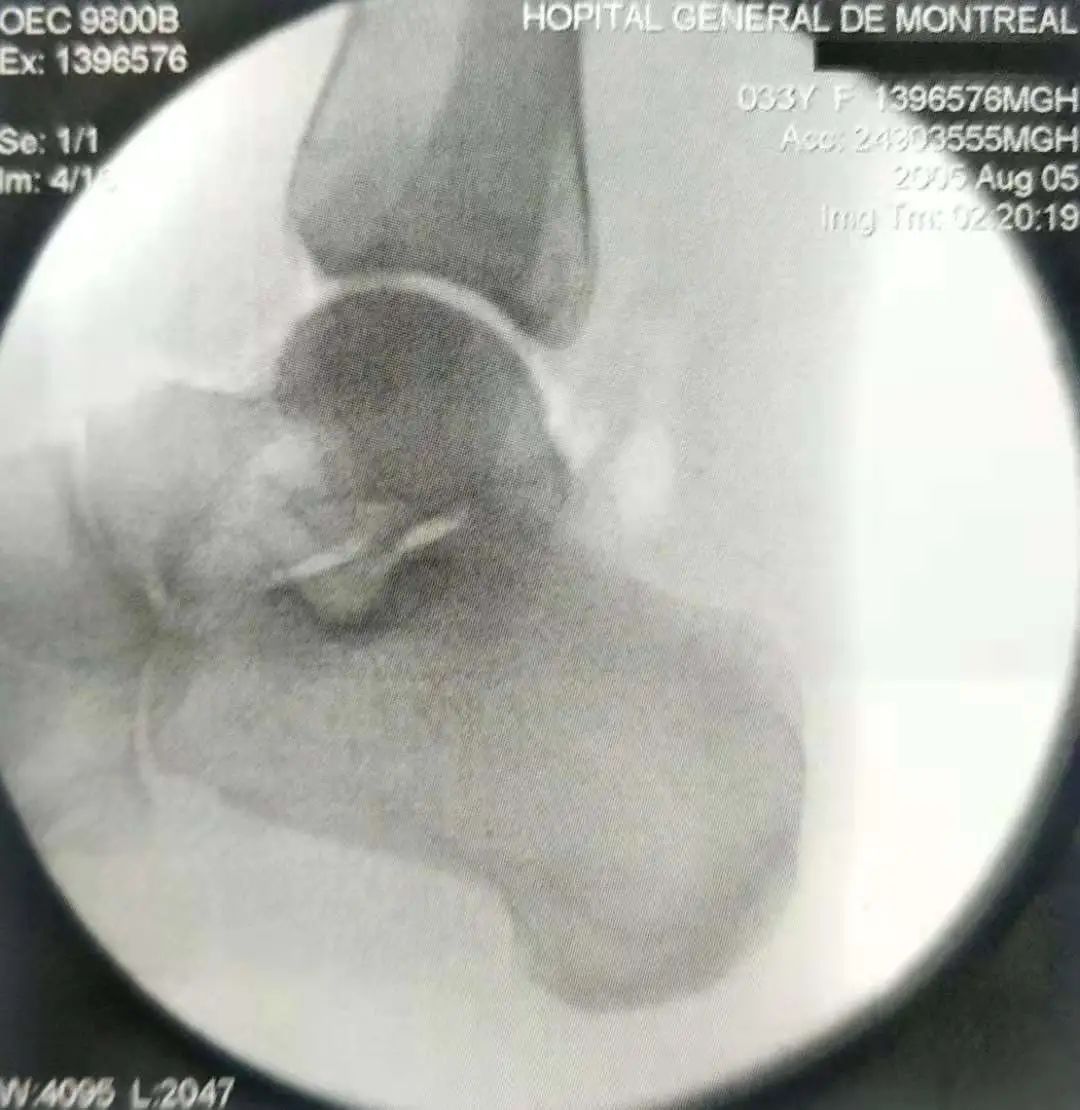

- 术中通常需要使用C形臂X线机。

▲ 侧位片检查

- 如果没有术中C形臂,则可用多角度X线平片来代替。